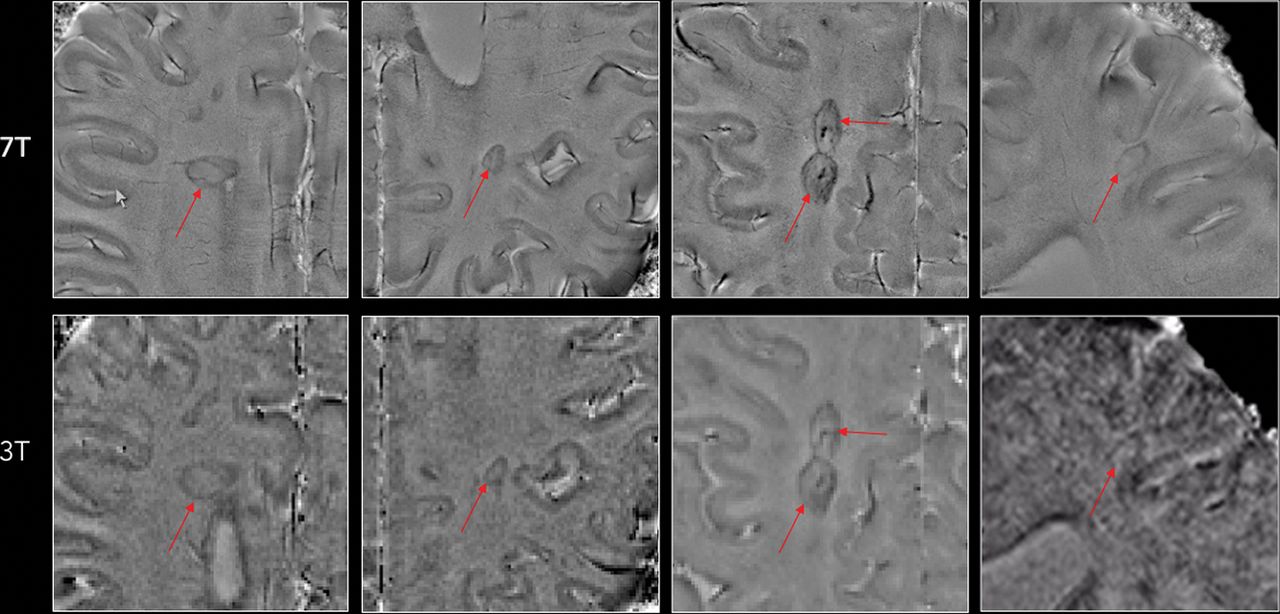

Representative concordant and discordant cases are shown in Figs 1⇓–3.

Representative examples of MS lesions in which a paramagnetic rim (red arrows) can be easily seen on both 7T and 3T phase images. Note the superior image quality at 7T in at least 3 of the 4 examples.